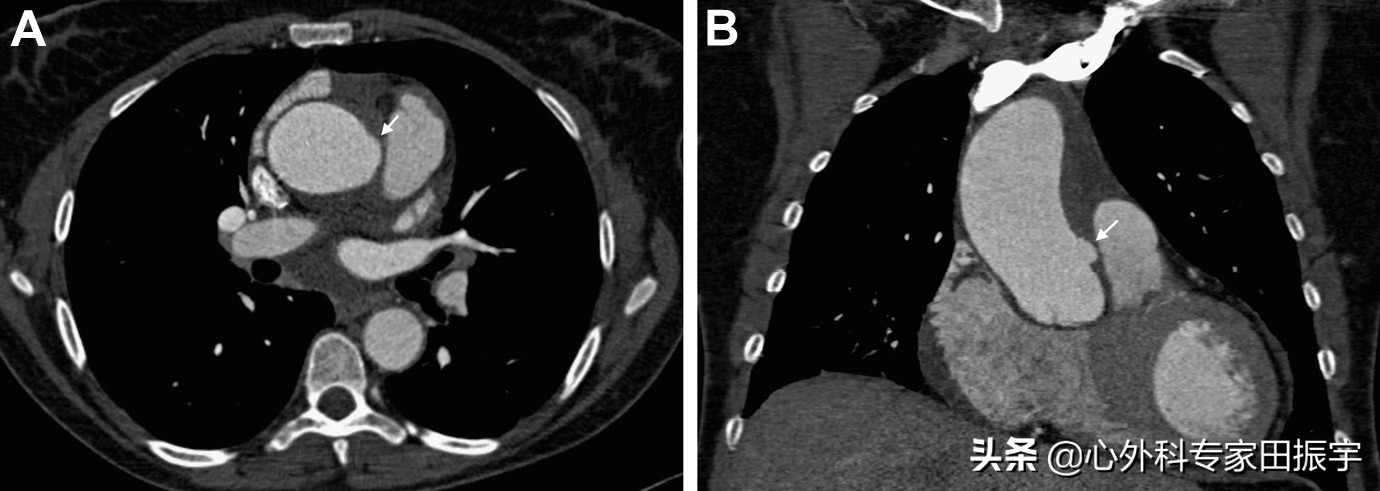

主动脉壁间血肿溃疡状凸起

图1 一名42岁的妇女在休息时出现胸痛。轴向 (A) 和冠状 (B) 方向上的增强 CT 图像显示为 A 型主动脉壁内血肿,升主动脉壁内有类似溃疡的小投影(箭头)。